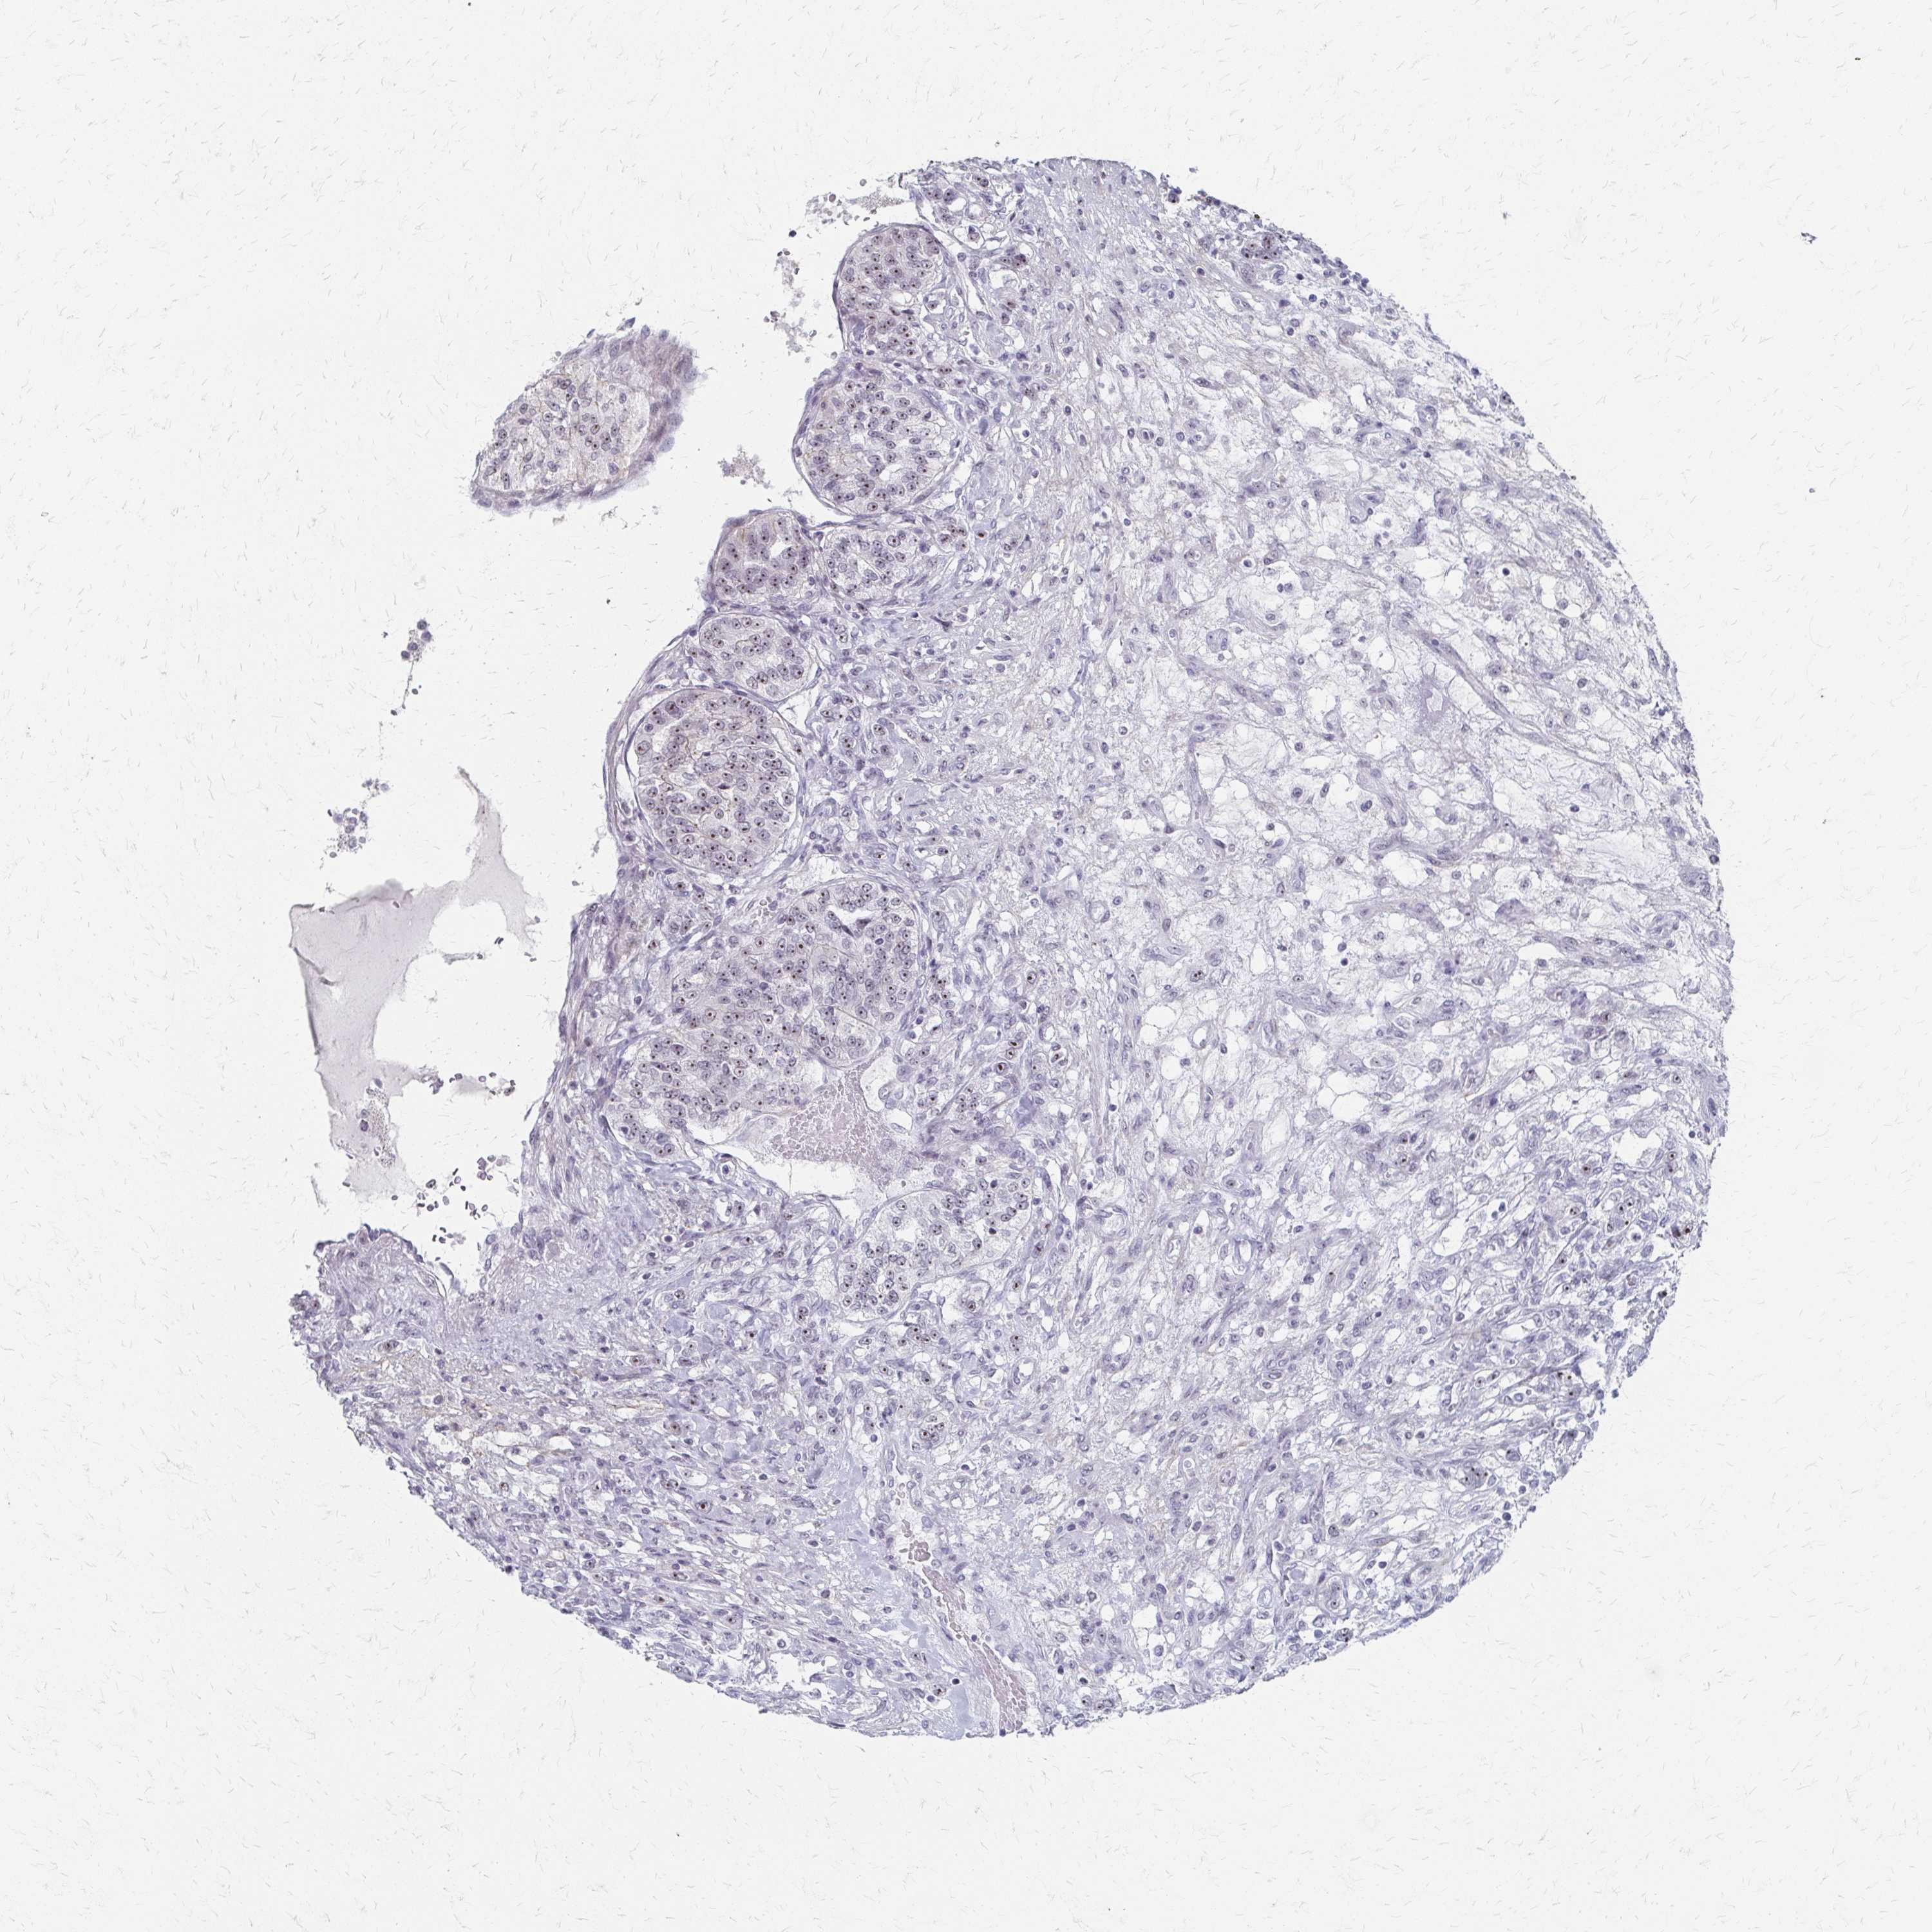

CANCER RENAL CANCER Show tissue menu

Renal cancer

Kidney chromophobe